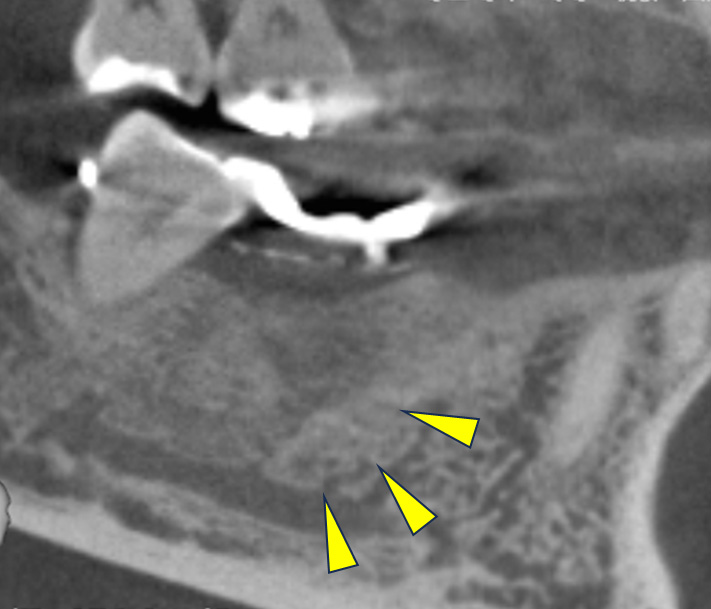

親抜歯後、歯ぐきは治癒しました。しかし、インプラント治療のためには骨が不足していました。

CT画像 -

骨移植(人工骨+メッシュプレート)を行い、骨を造りました。